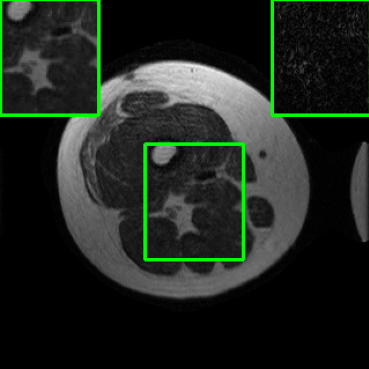

Performance on the Stanford FSE Dataset: We also performed image reconstructions with the Stanford multi-coil FSE dataset, which is a smaller dataset. We used same settings for the networks and training as in Section IV-A. Table III shows that LONDN-MRI significantly outperforms the globally learned MoDL network at both 4x and 8x acceleration. This indicates benefits for the proposed framework for smaller, more diverse datasets. Figs. 7 and 8 display visual comparisons that show the LONDN-MRI scheme recovering sharper features than the globally learned network.

| Ground Truth | Initial | Global | LONDN-MRI | LONDN-MRI | Oracle |

| (1 iteration) | (2 iterations) | ||||

![]() |

| PSNR = dB | PSNR = 19.41 dB | PSNR = 26.52 dB | PSNR = 27.76 dB | PSNR = 27.85 dB | PSNR = 27.92 dB |